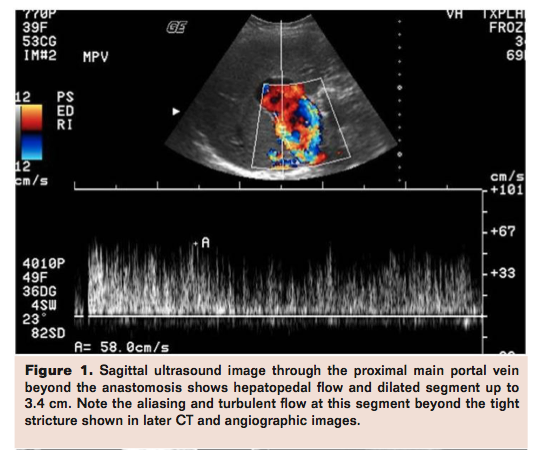

Patency of the portal vein may be evaluated with DUS and or cross-sectional imaging. Figures 1-4 show images from a case of a 34-year-old female with a history of liver transplant in 1994 due to autoimmune hepatitis and hepatitis, who presented with upper abdominal pain. Imaging evaluation with ultrasound followed by portal angiography was undertaken. Figures 1 and 2 show evaluation of patency.

Karakayali et al examined late onset PVS after living donor transplant in the pediatric population. They found that PVS can be asymptomatic in some cases.7 Moreover, splenomegaly and low platelet count can be important markers of PVS and early detection using these markers can prevent graft loss.